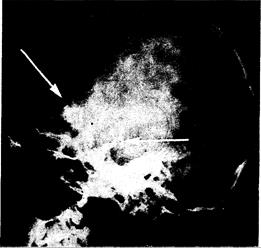

Выявление на плоскостных рентгенограммах черепа на основании узелковой или криволинейной кальцификации в супраселлярной области позволяет заподозрить краниофарингиому (рис. 321 -14). Подобную кальцификацию обнаруживают у 80—90% больных детей, но менее чем у 50% взрослых больных. Хотя турецкое седло может быть увеличено и растянуто, кортикальная кость обычно сохраняется. При внутриселлярных краниофарингиомах спинка турецкого седла часто смещена назад. При КТ-сканировании почти у всех больных детей и у 80% взрослых больных отчетливо видны кистозные участки с кольцом узелковой кальцификации. Некистозные области после введения контрастного вещества так или иначе увеличиваются; у детей это особенно заметно.

Рис. 321-14. Боковая рентгенограмма черепа (в боковой проекции)у больного с краниофарингиомой.

Можно видеть плотную кальцификацию в области, расположенной над турецким седлом (стрелка).